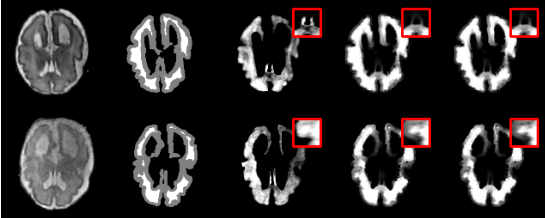

强先验方法:目前主流的深度学习方法通常需要大量的像素级标注数据(强先验),但这在医学影像领域获取成本高昂且困难。 弱先验方法:利用如三分图这样的弱先验信息进行抠图,标注成本低,这些方法包括: l 基于传播的方法:依赖于平滑性假设,即像素在特定区域变化平滑。如果自然图像中存在违反该假设的情况(如纹理复杂),预测精度会受限。 l 基于采样的方法:依赖于从未知像素的周边选取像素对子集。如果子集中的像素对与最优解差异较大,抠图精度会迅速下降。 l 优化类方法:将医学图像抠图问题建模为像素对选择问题,从整个像素对集合中选择像素对。进化算法因其强大的全局优化能力被用于求解像素对选择问题,能够更广泛地搜索解空间,而不局限于局部区域或特定的初始采样质量。然而,像素对选择问题的决策空间规模随着未知像素数量的增加呈指数级增长,增加了进化算法陷入局部最优的风险,降低了进化算法的求解效率。 2. 方法概述 针对上述挑战,智能算法研究中心与南方医科大学附属南方医院庄宝雄教授团队合作提出了一种用于求解医学图像抠图问题的微搜索进化优化框架[1][2]。 微搜索假设被广泛应用于众多优化问题的求解中,如滤波器自动调参问题[11],双层车辆路径规划问题[10],约束优化问题[9]等。实验结果验证了微搜索假设能够帮助算法大幅度提升算法求解问题的效率。在微搜索假设中,对于任意一种算法,决策空间(决策集)中存在一个规模远小于决策空间(决策集)的子空间(子集),该子空间(子集)由算法的可行解组成,且包含了优化问题的最优解。该子空间(子集)被称为有效决策子空间(子集)。 研究团队观察到,在医学图像抠图问题中,相似的子问题(即相似的未知像素)其目标空间也具有高度的相似性(图 1),目标函数在梯度方向和数值分布上都高度一致。这意味着进化算法在优化相似子问题时,同一个解所在的局部区域为进化算法提供的启发式信息是子问题无关的。

图 1 相似子问题的目标空间等高线对比

实验结果表 2表明,在仅提供Trimap的弱先验条件下,微搜索进化优化医学图像抠图算法在均方误差和梯度误差上,优于大多数对比方法。可视化结果(图 4)也显示,该方法能更准确地恢复前景与背景极其相似的模糊边缘区域。 表 2 弱先验测试场景中抠图预测指标对比

图 4 有无微搜索策略的抠图预测结果可视化对比